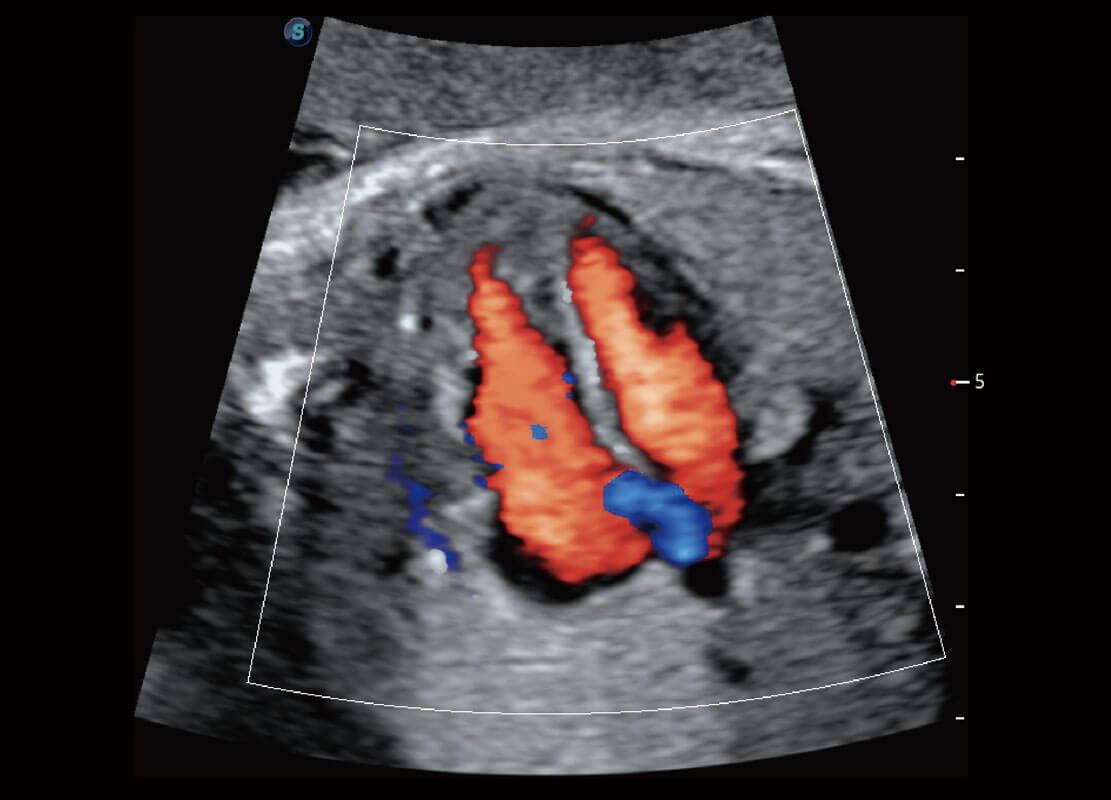

胎儿体循环